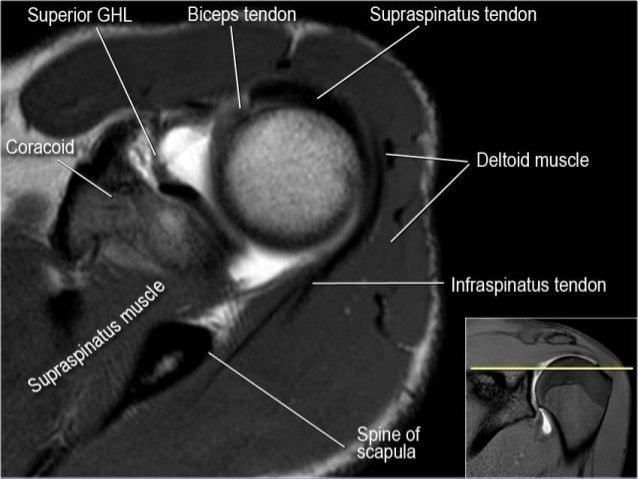

Mri of shoulder anatomy dr. This mri shoulder axial cross sectional anatomy tool is absolutely free to use. An mri of the shoulder of a healthy subject was performed in the 3 planes of space coronal axial sagittal commonly used in osteoarticular imagery with two weightings most commonly used to explore the musculo skeletal pathology of the shoulder.

Use the mouse scroll wheel to move the images up and down alternatively use the tiny arrows on both side of the image to move the images on both side of the image to move the images. Use the mouse to scroll or the arrows. This webpage presents the anatomical structures found on shoulder mri.